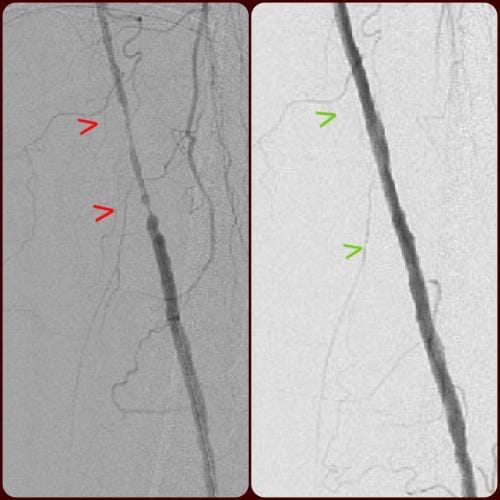

During these procedures: Sedation is given to help you relax. Next, a tiny tube is gently inserted in an artery, usually in the groin or upper thigh area. You will be given a local anesthetic to numb the area where the tube will be inserted. It is then guided through the blood vessel toward the disease artery. When it’s in place, a dye is injected through the catheter to visualize the arteries. An X-ray is taken to help the physician pinpoint the area that is blocked or narrowed. The physician then uses tiny wires and catheters to get through the diseased vessels. Depending on the images treatment may then be performed.

Angioplasty — a special catheter that has a balloon on one end is advanced into the diseased artery. This is temporarily inserted through the narrowed artery and inflated to flatten the plaque against the artery wall, opening the artery and restoring blood flow.

Stent placement —a stent is a small, expandable, leg pain angioplasty stent los Angeles san diegomesh-like tube that supports the artery and helps to keep it open. Implanting a stent does not require open surgery. The doctor inserts a catheter into an artery in your arm or leg, similar to the balloon angioplasty procedure. A specially designed catheter delivers the stent to the narrow area in the artery. The stent is expanded, flattening the plaque against the artery wall and holding the artery open with a mesh tube. The catheter used to deliver the stent is then removed, but the stent stays in your artery permanently to maintain healthy blood flow.

Atherectomy — a specialized catheter that modifies the plaque in the arteries. Unlike angioplasty and stenting, which are designed to move plaque to the sides, atherectomy involves cutting and removing or sanding down the plaque from the artery, restoring normal blood flow.